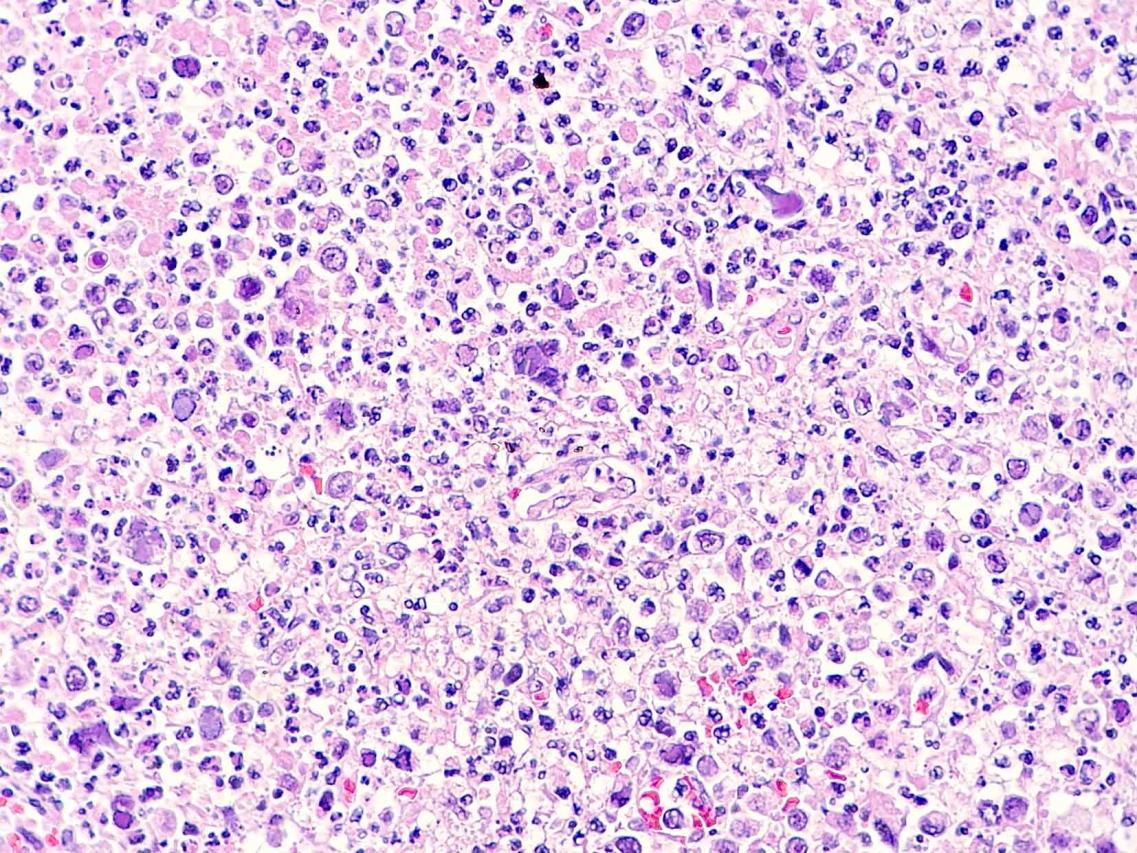

Este estudio, publicado en Transboundary and Emerging Diseases (2020; doi:10.1111/tbed.13713), ilustra el papel de la patología como herramienta de apoyo a los programas de conservación para especies en peligro de extinción. En este caso, la detección de dos herpesvirus presumiblemente nuevos en visones europeos se realizó a raíz del diagnóstico de un caso de linfoma principalmente neural/perineural con cuerpos de inclusión característicos de herpesvirus intralesionales en un visón europeo procedente del programa de cría en cautividad de esta especie amenazada. Estos virus podrían tener una influencia en el desarrollo de ésta y otras enfermedades que afectan a esta especie en cautividad y, por lo tanto, afectar a sus poblaciones.